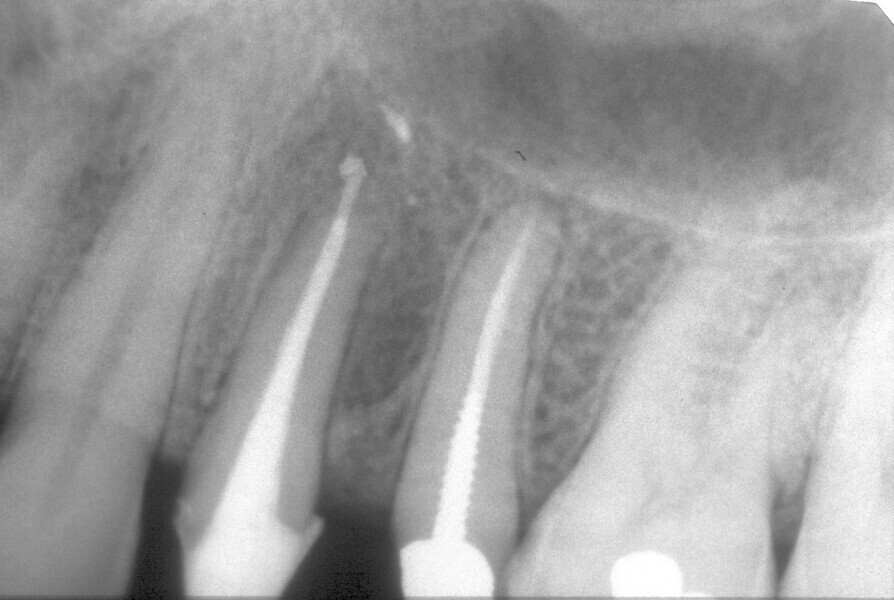

Buccal root of the bifurcated maxillary premolar—a danger zone during root canal therapy